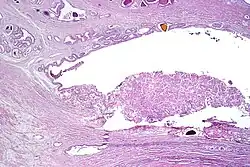

Intraductal carcinoma

Intraductal carcinoma of the prostate gland (IDCP), which is now categorised as a distinct entity by WHO 2016, includes two biologically distinct diseases. IDCP associated with invasive carcinoma (IDCP-inv) generally represents a growth pattern of invasive prostatic adenocarcinoma while the rarely encountered pure IDCP is a precursor of prostate cancer.[20] The diagnostic criterion of nuclear size at least 6 times normal is ambiguous as size could refer to either nuclear area or diameter. If area, then this criterion could be re-defined as nuclear diameter at least three times normal as it is difficult to visually compare area of nuclei.[20] It is also unclear whether IDCP could also include tumors with ductal morphology.[20] There is no consensus whether pure IDCP in needle biopsies should be managed with re-biopsy or radical therapy. A pragmatic approach would be to recommend radical therapy only for extensive pure IDCP that is morphologically unequivocal for high-grade prostate cancer.[20] Active surveillance is not appropriate when low-grade invasive cancer is associated with IDCP, as such patients usually have unsampled high-grade prostatic adenocarcinoma.[20] It is generally recommended that IDCP component of IDCP-inv should be included in tumor extent but not grade.[20] However, there are good arguments in favor of grading IDCP associated with invasive cancer.[20] WHO 2016 recommends that IDCP should not be graded, but it is unclear whether this applies to both pure IDCP and IDCP-inv.[20]

-

Intraductal carcinoma of the prostate with an infiltrative growth pattern may be morphologically difficult to distinguish from invasive cancer. One focus shows comedonecrosis (arrow), morphologically suggesting Gleason pattern 5 invasive carcinoma (a haematoxylin and eosin, b CK5/6)[20] -

Intraductal carcinoma of the prostate with very patchy basal cells identified by immunohistochemistry. At least some of the glands lacking basal cell immunoreactivity represent intraductal rather than invasive carcinoma (a haematoxylin and eosin, b CK 5/6)[20]

Ductal adenocarcinoma may have a prominent cribriforming architecture, with glands appearing relatively round, and may thereby mimic intraductal adenocarcinoma, but can be distinguished by the following features:[10]